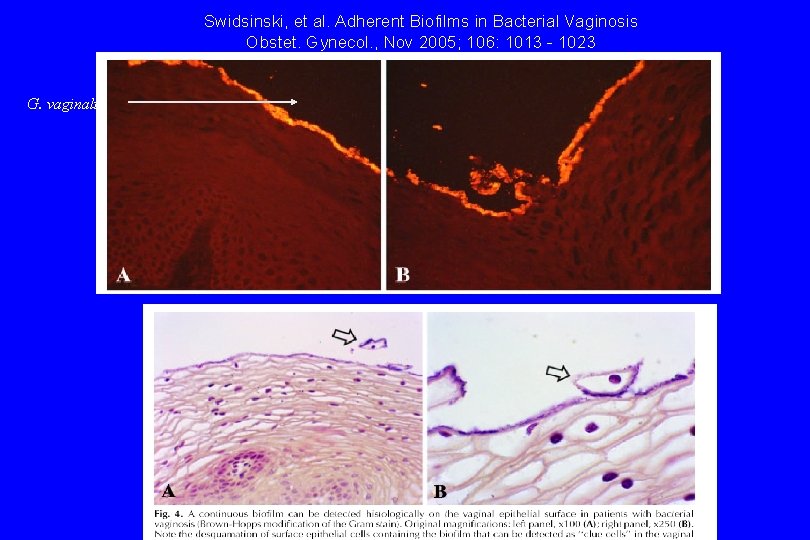

Swidsinski, et al. Adherent Biofilms in Bacterial Vaginosis Obstet. Gynecol. , Nov 2005; 106: 1013 - 1023 G. vaginalis